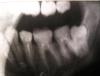

Krio Опубликовано 21 августа, 2012 Поделиться Опубликовано 21 августа, 2012 Здравствуйте!Уважаемые доктора, проконсультируйте, пожалуйста.Прилагаю снимок угла челюсти.Сегодня ходила к терапевту и хирургу (из-за нечастых, нелокализованных и не очень болезненных ощущений в щеке), оказалось, для нижней правой 8-ки нет места.Хирург сказал, что пока ничего делать не нужно. Но если удалить 7-ку, то 8-ка может встать на ее место (а слева у меня именно так и произошло). но сейчас удалять 7-ку не советует, т.к. "она хорошо пролечена". но когда он стал рассказывать, как удаляется 8-ка -с рассверливанием челюсти и пр., мне стало нехорошо и сразу захотелось удалить 7-ку вместо 8-ки (вроде не так страшно).а может быть, имеются какие-то альтернативные способы исправить ситуацию?неужели просто ждать, какой из этих двух зубов воспалится раньше, и действовать, исходя из этого?сам зуб не прорезался, есть бугорок практически уже в области щеки.если имеет значение, мне 30. буду очень признательна за любые ваши мнения.Анна 1 Ссылка на комментарий

Krio Опубликовано 24 августа, 2012 Автор Поделиться Опубликовано 24 августа, 2012 Zborzh, мне говорили разные люди, что это лучший (или один из 2 лучших) врач в нашей области, работает в областной клинике, ЧЛХ. А что Вы имеете в виду, что по снимку всё не так страшно? он мне говорил, что если при таком расположении 8-ки не выпиливать кость (сверху, видимо - разве она там не мешает, судя по снимку?), а полагаться на силу, у женщин очень часто ломается челюсть. недавно моему другу делали такую же операцию, выпиливали кость. он второй месяц в себя прийти не может, боли и онемение губы остается.. так что мне совсем не хочется повторять этот опыт! помню, как мне лет в 18 удаляли 7-ку с другой стороны - не знаю, как пережила, меня там трое держали.хочется проконсультировать с максимальным кол-вом специалистов, а у нас в городе хирургов-стоматологов очень мало, вот и решила посоветоваться заочно.. главный вопрос: откладывать до появления проблемы (воспаления или болей) или что-то делать, не дожидаясь ее? сейчас же по снимку воспаления у 8-ки нет? а у основания 7-ки гранулема, мне сказали... Ссылка на комментарий